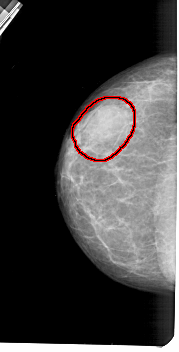

A_1419_1.LEFT_CC

LEFT_CC LINES 5266 PIXELS_PER_LINE 2671 BITS_PER_PIXEL 12 RESOLUTION 43.5 OVERLAY

FILE: A_1419_1.LEFT_CC.OVERLAY

TOTAL_ABNORMALITIES 1

ABNORMALITY 1

LESION_TYPE MASS SHAPE OVAL MARGINS OBSCURED

ASSESSMENT 4

SUBTLETY 4

PATHOLOGY BENIGN

TOTAL_OUTLINES 1

BOUNDARY